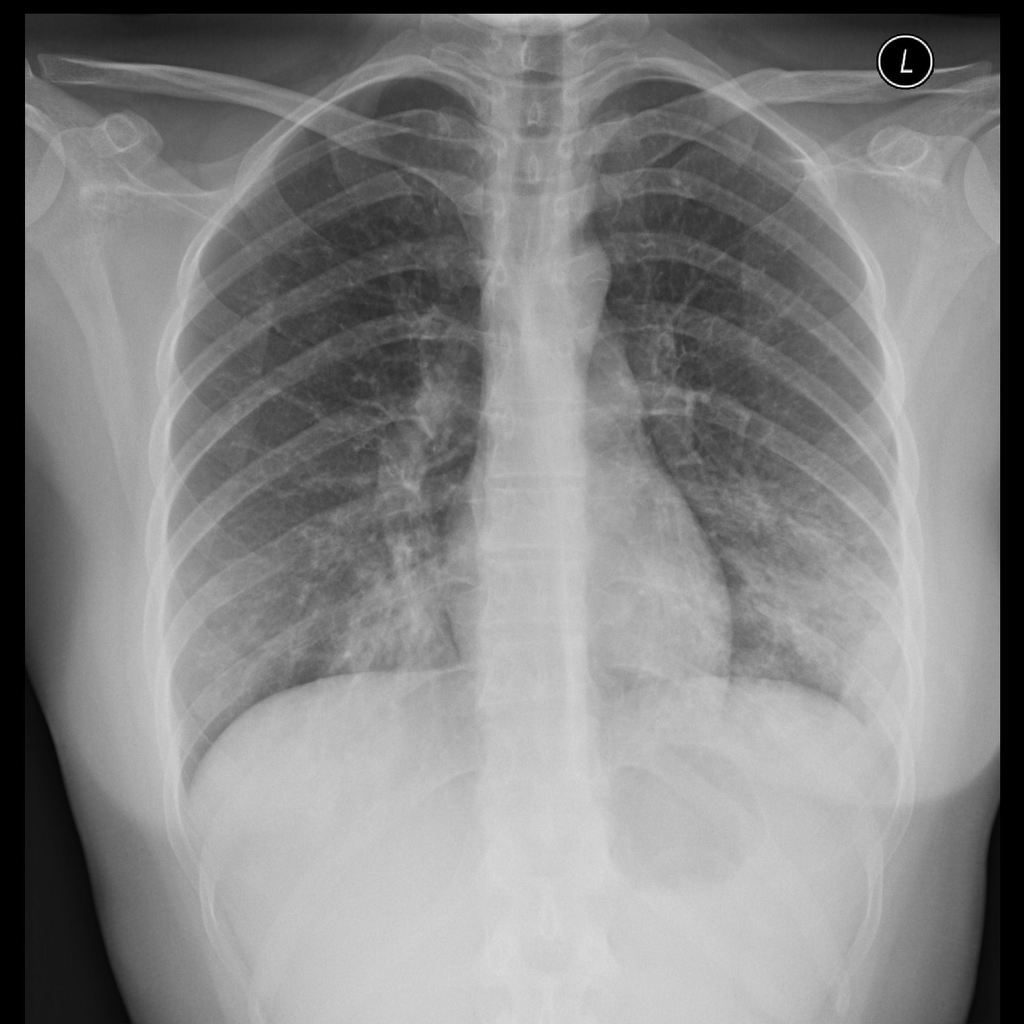

Rx: broncopneumonia ou lobar

Rx: infiltrado intersticial